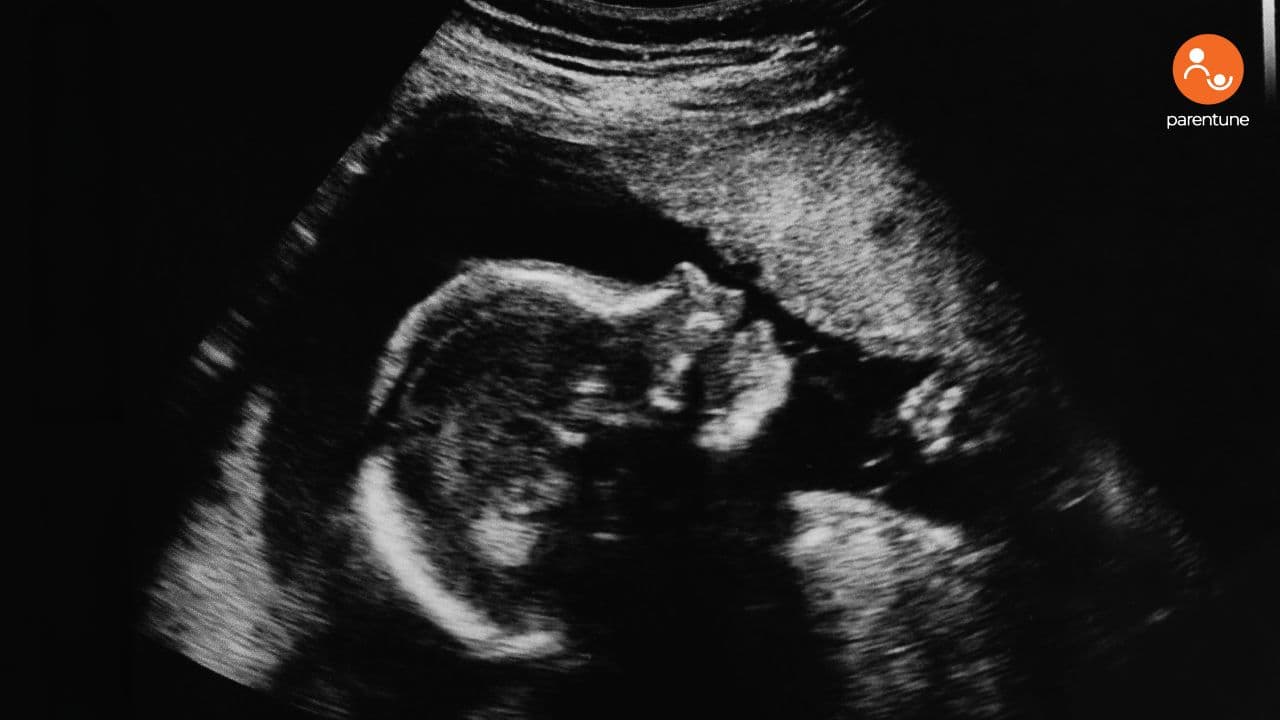

What Does An Ultrasound Show? And Why It Matters

Ultrasound is the window that makes the invisible visible.

Doctors use it to:

-

Confirm fetal heartbeat

Locate the bleed (how close is it to the placenta?)

Measure its size (this matters more than you’d think)

Smaller bleeds tend to resolve quickly. Larger ones—especially near the placenta—may require more monitoring.